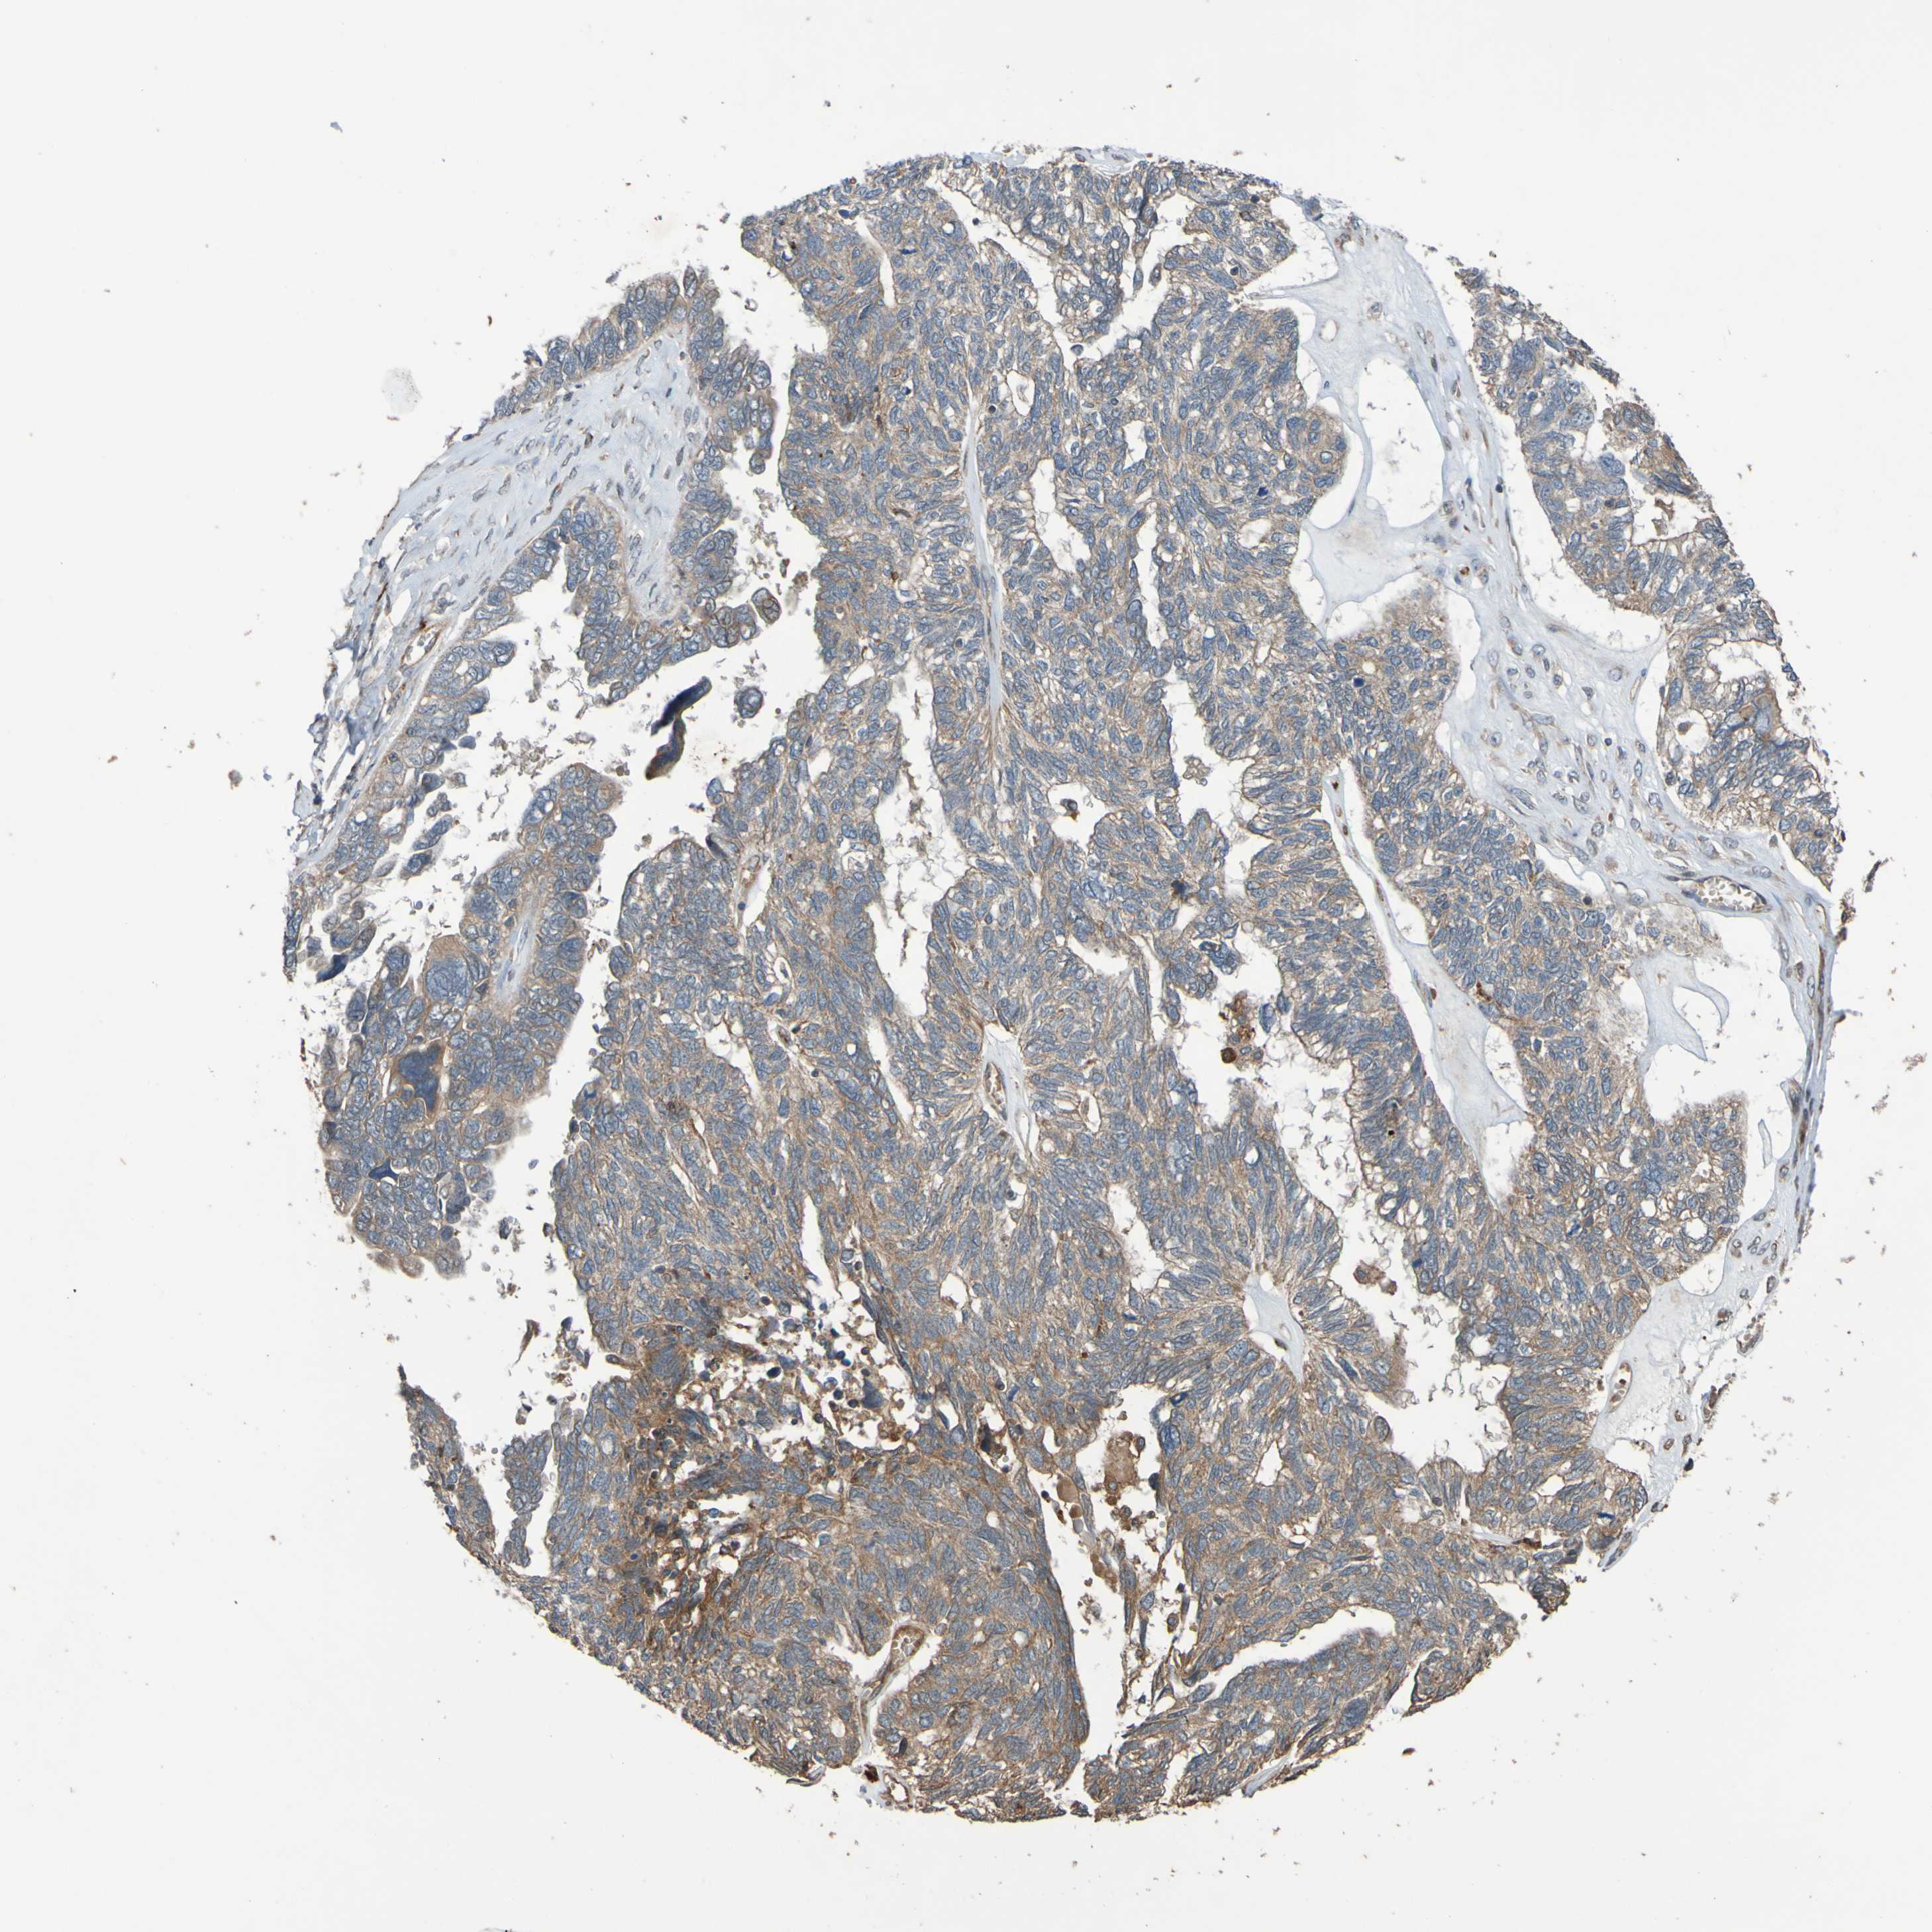

OVARIAN CANCER - Protein expressioni

A mouse-over function shows sample information and annotation data. Click on an image to view it in a full screen mode. Samples can be filtered based on level of antibody staining by selecting one or several of the following categories: high, medium, low and not detected. The assay and annotation is described here.

Note that samples used for immunohistochemistry by the Human Protein Atlas do not correspond to samples in the TCGA dataset.

Antibody stainingi

Antibody staining in the annotated cell types in the current human tissue is reported as not detected, low, medium, or high, based on conventional immunohistochemistry profiling in selected tissues. This score is based on the combination of the staining intensity and fraction of stained cells.

Each image is clickable and will lead to virtual microscopy that enables deeper exploration of all samples and also displays staining intensity scores, fraction scores and subcellular localization as well as patient and tissue information for each sample.

Antibody CAB010911

Cystadenocarcinoma, serous, NOS

Carcinoma, endometroid

Cystadenocarcinoma, mucinous, NOS

Carcinoma, NOS